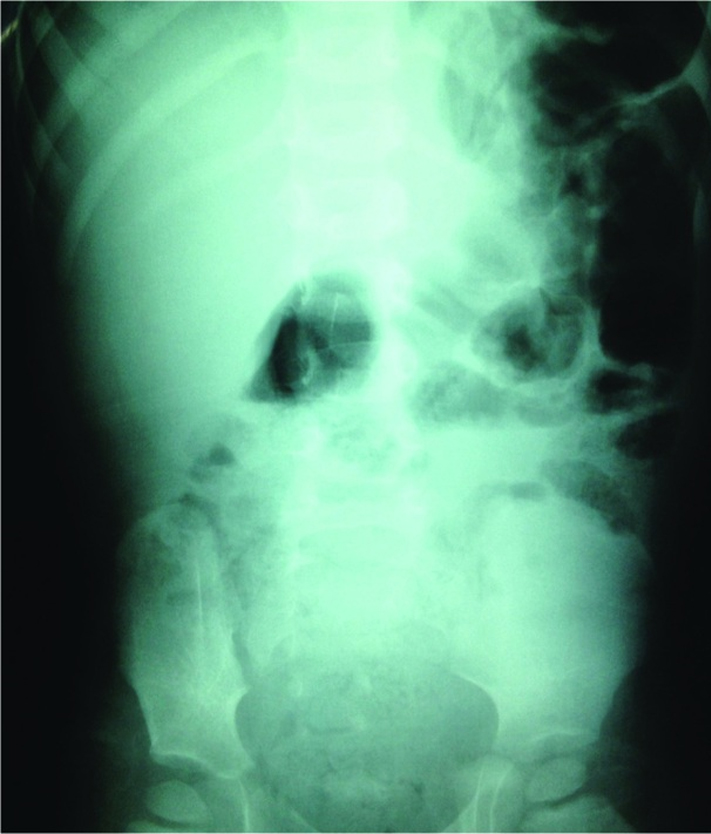

Hình ảnh X-quang bụng cháu bé ngày đầu tiên khi uống nhầm thủy ngân

Và sau 7 ngày cho thấy lượng thủy ngân đã được đào thải hết ra ngoài.